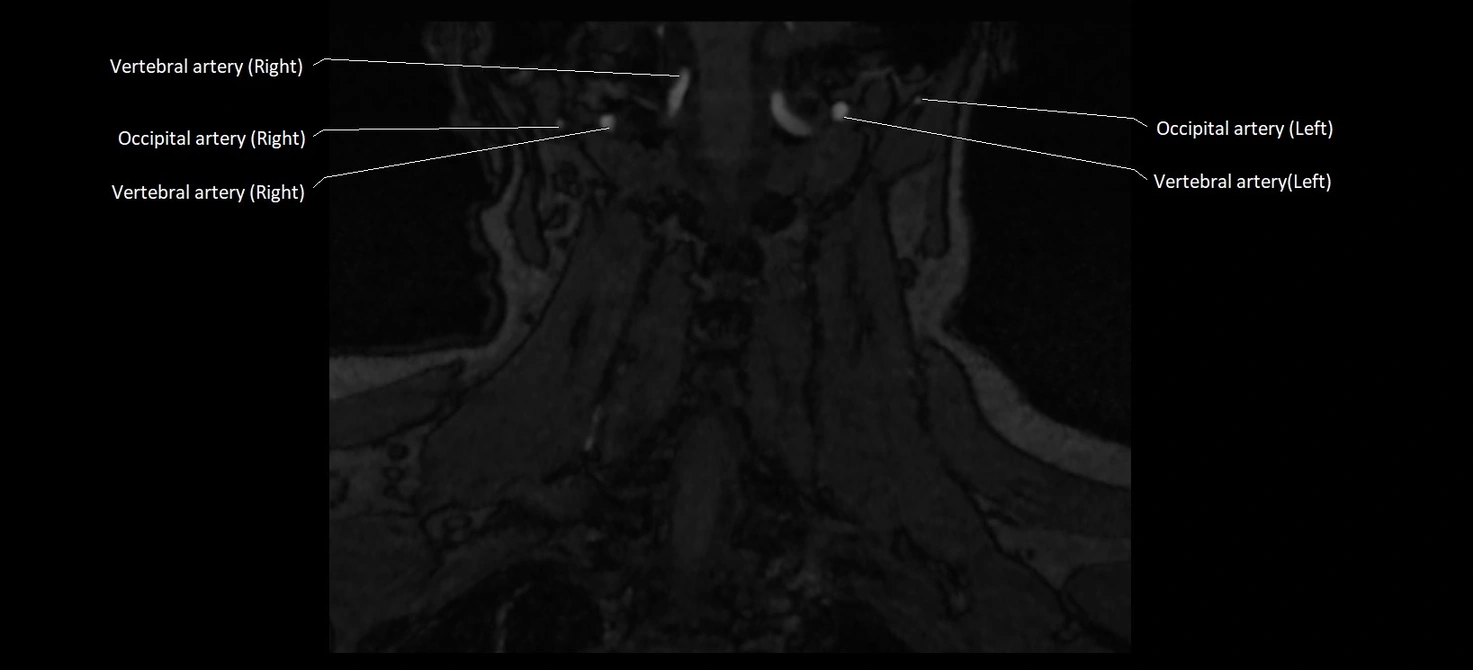

CT image

image